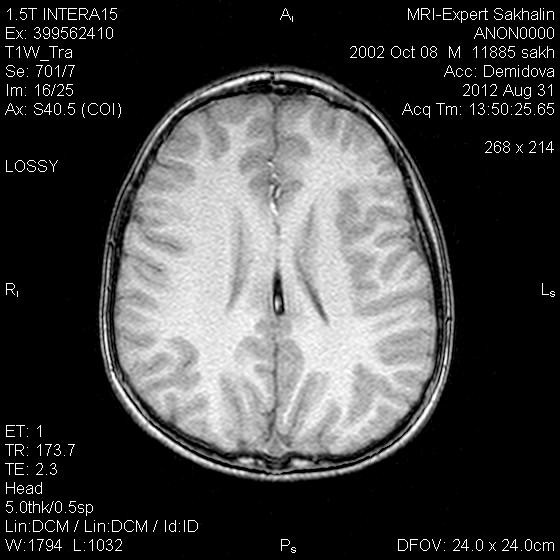

Сегодня проходил исследование ребенок с жалобами на головную боль.В анамнезе-удар головой около 1 мес.назад.Мама сообщила , что при родах на УЗМ выявили кровоизлияние в мозолистое тело, причем сообщила уже после исследования, когда мой мозг был на грани истерии-это уже второй случай за неделю, а я не могу ничего толком понять-это тромбированный сосуд либо кровоизлияние?Обоим рекомендовала проведение МР-ангио.

Липома мозолистого тела. КТ разрешит все сомнения.

может перикаллёзная липома. Надо жироподавление было поставить. тоже разрешит.

Перикаллезные липомы бывают линейные (криволинейные, повторяющие формы мозолистого тела) и узловые.